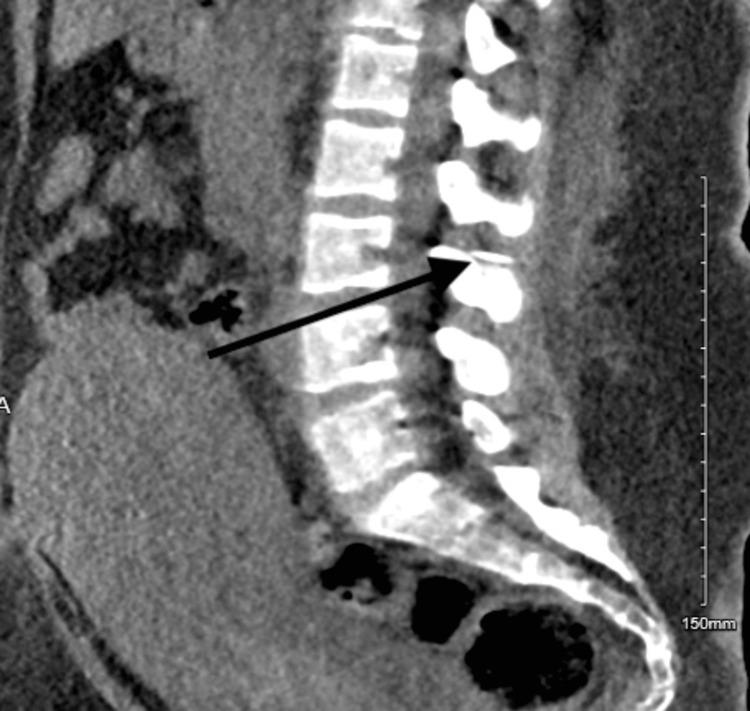

The breakage of the epidural catheter is an alarming, rare, yet well-known complication. Despite the advances in modern imaging technologies, visualization of the broken catheter remains challenging, and surgical intervention might be necessary to remove the broken catheter. We report a case of a broken epidural catheter post-vaginal delivery, which was managed by surgical intervention.

Broken Epidural Catheter After Vaginal Delivery.